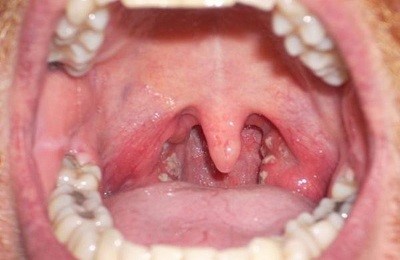

Характерный признак вирусного заболевания – множественные высыпания красного цвета в ротовой полости. По внешнему виду сыпь похожа на водянистые образования, которые начинают вскрываться через 3-4 часа после появления.

После вскрытия пузырьков на поверхности слизистой оболочки образуются эрозии и язвочки, заживающие длительное время (до 7-8 дней). При этом пораженный участок отекает. Ребенок чувствует боль и дискомфорт при глотании слюны и потреблении пищи. Симптомы недуга постепенно усиливаются, к болевым ощущениям присоединяется зуд и увеличение шейных лимфоузлов.

Иногда при герпесной ангине развивается везикулезный стоматит – сыпь возникает на языке, внутренней стороне шеек и деснах. Несмотря на высокую температуру, стоматит протекает без осложнений и завершается через 6 дней, не оставляя после себя шрамов и рубцов на тканях.